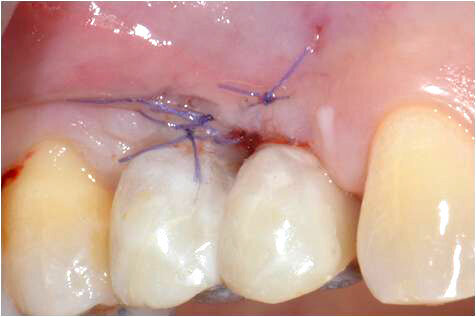

La fibromucosa rimossa è stata disepitelizzata e, mediante sutura riassorbibile 6-0 con punti a materassaio orizzontale, fissata in due tasche chirurgiche di dimensione idonea, sovrastanti al margine libero della cresta alveolare. Le tasche sono state realizzate mediante incisione a spessore parziale del tessuto gengivale apicale al margine libero della sella edentula e in corrispondenza dei due siti implantari, in modo da simulare a guarigione avvenuta la bozza radicolare (Fig. 6). L’incisione a spessore parziale favorisce un rapido attecchimento del tessuto connettivo innestato per la presenza di un doppio letto vascolare (periostale sull’aspetto interno e mucoso sull’esterno). La chiusura dei due siti riceventi mediante punti singoli protegge il connettivo in esse contenuto dalla contaminazione della saliva e dei batteri nelle prime fasi della guarigione. Al termine della fase chirurgica sono state applicate due corone provvisorie avvitate, ottenute adattando due corone preformate su abutment provvisori in titanio (Alpha-Bio Tec, Israele) (Figg. 7, 8).

Fig. 6_Il connettivo prelevato dalla cresta è stato inserito e stabilizzato mediante sutura riassorbibile nelle due tasche, realizzate nella mucosa al lato dei siti implantari.

Fig. 8_Al termine della chirurgia la paziente è stata dimessa con due corone provvisorie avvitate.